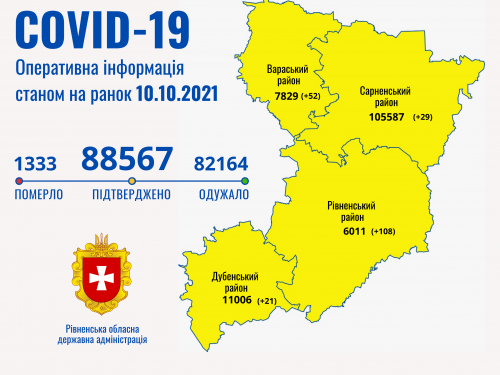

Коронавірус повертається: як стрімко зростає кількість хворих на Рівненщині (ВІДЕО)

Пів тисячі - у важкому стані, 9 жителів Рівненщини померли за добу від коронавірусу